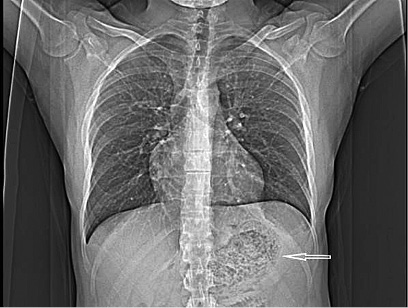

A thirty two years old male patient presented to our surgery department with complain of postprandial abdominal pain, early satiety and occasional vomiting episodes. He lost 5–6 kg in the past 6 months. The symptoms were present for the last 1 year. No comorbidity was reported. Previously he underwent a gastroscopy in another hospital where a stomach bezoar and large ulcer was diagnosed (Figure 1). Plain x-ray (Figure 2), computerized tomography (CT) scan (Figures 3 and 4) and gastroscopy were conducted in our institution. The gastroscopic examination reported giant rough bezoar impossible for endoscopic retrieval.

Figure 2. Plain chest x-ray with visible mass in the stomach